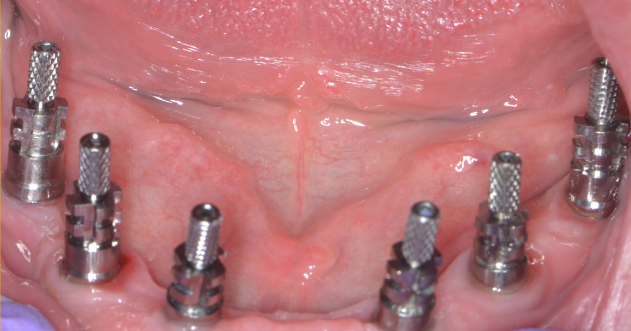

După acest interval lucrarea provizorie se îndepărtează, în fiecare implant se montează câte un dispozitiv necesar realizării amprentelor (Fig. 3.6.7) care vor servi tehnicianului dentar pentru realizarea punții definitive (Fig. 3.6.8 și Fig. 3.6.9). Realizarea acesteia se face în câteva zile, interval în care pacientul va continua să poarte lucrarea provizorie realizată inițial.

Lucrarea finală se va înșuruba pe componentele protetice ale implanturilor (Fig. 3.6.10 și 3.6.11), iar perforațiile de acces pentru șuruburi (Fig. 3.6.12) vor fi acoperite cu material compozit (Fig. 3.6.13). După fixarea definitivă (Fig. 3.6.14) puntea poate fi oricând detașată de către medicul dentist la nevoie, prin simpla îndepărtare a materialului compozit și desfiletarea șuruburilor de fixare.